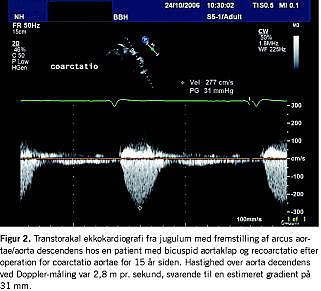

Associeret kardiovaskulær malformation ses hos op mod 20% af patienterne med BAK. Eksempler herpå omfatter coarctatio aortae, ventrikelseptumdefekt og persisterende ductus arteriosus. Coarctatio aortae er associeret med BAK i mere end 50% af tilfældene (Figur 2 ), og kombinationen giver en særlig risiko for aortadissektion [22, 24]. 15-18% af patienterne med Turners syndrom har BAK [25]. BAK har generelt en veludtalt hereditær komponent, der er forenelig med autosomalt dominant arvegang med varierende penetrans [1]. Resultaterne af nyere studier har dog peget mod en mere kompleks og heterogen arvelighed som basis for den familiære ophobning [26].

BAK er et almindeligt fund i ethvert ekkolaboratorium landet over og bør, jævnfør de associerede komplikationer hos en stor del af patienterne, give anledning til nøje planlægning af udredning og opfølgning. Hos børn og teenagere er kritisk aortastenose og endokarditis de hyppigste problemer, mens aldersgruppen fra ung voksen til midaldrende hyppigst har aortainsufficiens med eller uden forudgående aortaendokarditis eller aortadissektion. Fra femte dekade er aortastenose det typiske fund, og alt i alt estimeres det, at mindre end en tredjedel af patienter med BAK slipper for komplikationer/kirurgi i deres livstid [24]. Målet for ekkokardiografi er, som altid, at få den bedst mulige fremstilling af anatomien, herunder er det vigtigt ikke at lade sig snyde af den raphe, som altid opdeler den største af de to cuspes, og mistolke klappen for at være tricuspid. Når diagnosen BAK er stillet (og klapforholdene i øvrigt vurderet), skal der særligt fokuseres på udmåling af aortarod og aorta ascendens. Desuden fremstilles aortabuen fra jugulum med måling af Doppler-hastigheder over aorta descendens for udelukkelse af coarctatio aortae. Kirurgisk intervention skal overvejes, hvis aortaroden er over 5 cm og/eller hvis den årlige dilatationsrate er mere end 0,5 cm pr. år. Årlig billedundersøgelse anbefales hos patienter med aortarod på 4 cm eller derover [20]. Ved BAK med normalt fungerende klap og uden aortadilatation anbefales undersøgelse med 2-5 års intervaller. Primært anbefales ekkokardiografi og magnetisk resonans-skanning, som giver mulighed for samlet vurdering af torakale aortaforhold. Computertomografi giver sammenlignelig billeddannelse, men indebærer bestråling, hvilket set i lyset af patienternes ofte unge alder og behov for gentagne undersøgelser er uhensigtsmæssigt. Ved ambulant opfølgning skal der lægges særlig vægt på eventuel hypertension, som øger den i forvejen forhøjede risiko for aortadissektion og derfor nøje bør kontrolleres. Kadencen af klapdegeneration er hos BAK-patienter muligvis påvirkelig af hyperkolesterolæmi, og statinbehandling kan derfor overvejes. Der er dog ikke dokumentation for rutinemæssig statinbehandling uanset lipidprofil [17]. Resultaterne fra SEAS-undersøgelsen, hvori man tester simvastatin/ezetimib hos patienter med moderat aortastenose for teoretisk at hindre progression, kunne dog muligt ændre praksis på området. Resultater af undersøgelsen ventes i 2008 [26]. Rygning bør naturligvis under alle omstændigheder frarådes. Hvad angår det arvelige moment hos BAK-patienter, er der endnu ingen konsensus om anbefaling af familiescreening. Flere advokerer dog for tilbud om undersøgelse af førstegradspårørende, om end en cost-benefit-analyse af et sådant tiltag ikke er givet [4, 14, 27].